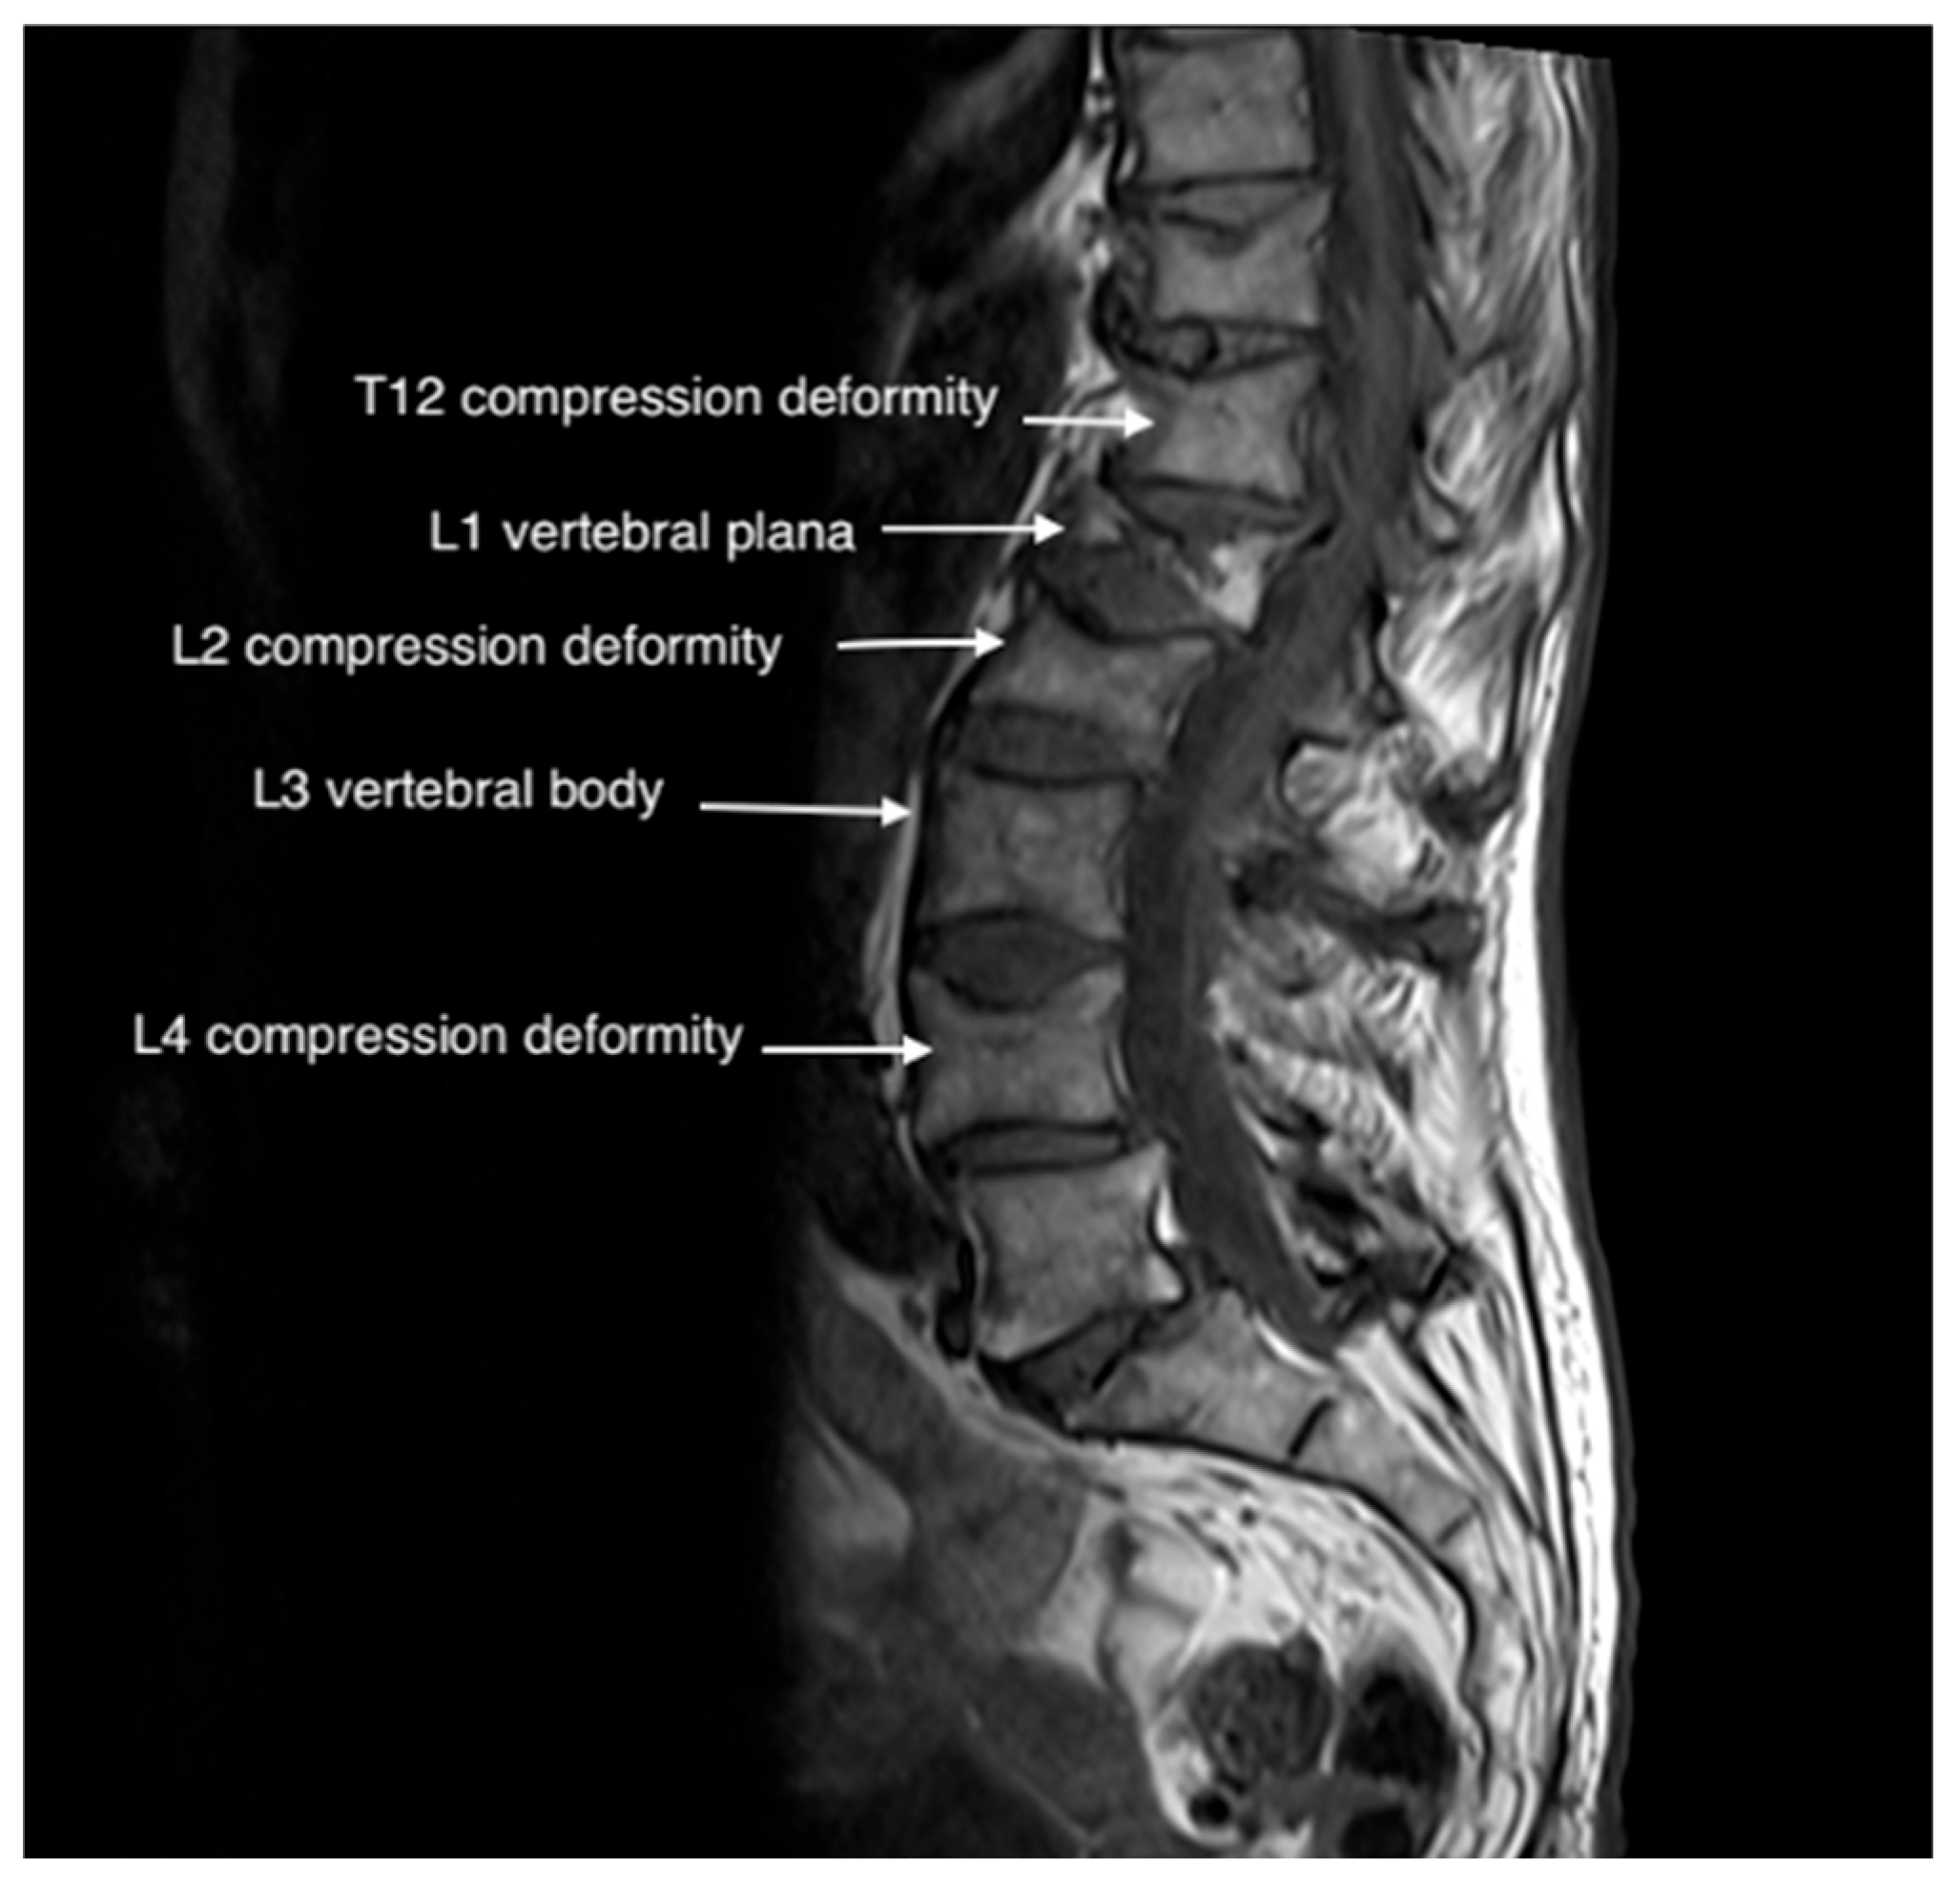

3. Case Presentations

3.1. Case 1

3.2. Case 2

3.3. Case 3

3.4. Case 4

| 1 | 80 | Female | L1 | Osteoporotic | T12 bilateral | Coronary Artery Disease, Prior Cardiac Arrest | 66% |

| 2 | 71 | Male | L4 | Pathologic | L3 bilateral | Diabetes Mellitus, Rheumatoid Arthritis, Degenerative Disk Disease, Multiple Myeloma | 75% |

| 3 | 85 | Female | L3 | Osteoporotic | L2 bilateral | Coronary Artery Disease, Hypertension, DM, Osteoarthritis | 60% |

| 4 | 85 | Female | L3 | Pathologic | L2 bilateral | Hypertension, Diabetes Mellitus, Osteoarthritis, Multiple Myeloma | 33% |